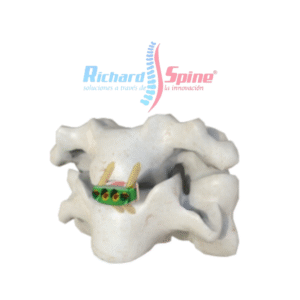

Caja de Fusión Intercorporal Cervical Anterior

- Implante de jaula de fusión intersomática cervical anterior

Placa de Fusión intercorporal cervical anterior

- La placa de fusión intercorporal cervical anterior es un dispositivo metálico utilizado en cirugía para estabilizar la columna cervical, específicamente en procedimientos de fusión intersomática anterior (ACIF). Esta placa se coloca en la parte frontal de las vértebras cervicales, después de la extirpación de un disco intervertebral dañado, para mantener la alineación y promover la fusión ósea entre las vértebras.